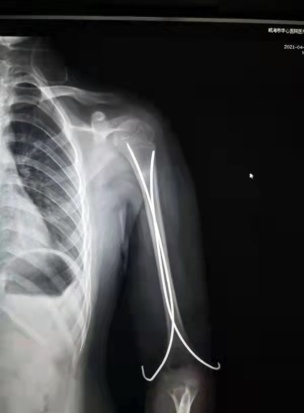

肱骨近端骨折闭合复位穿针术(术后) 锁骨骨折闭合复位穿针术(术前&术后)